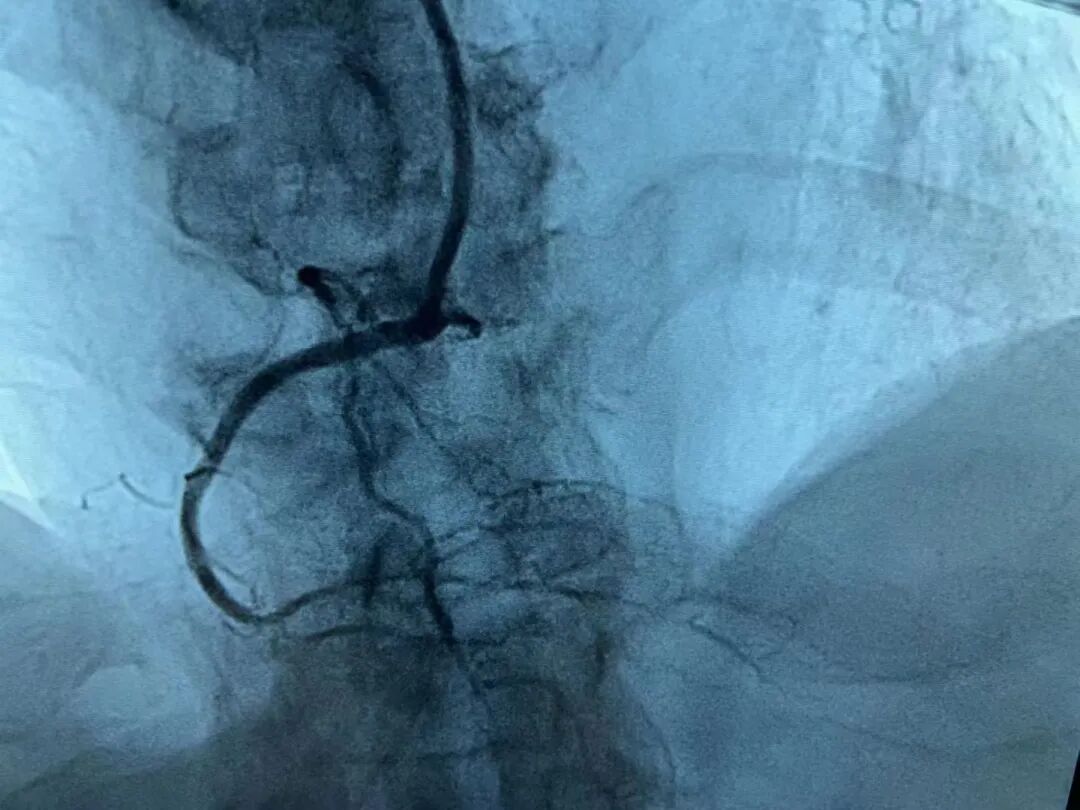

冠状动脉粥样硬化性心脏病是冠状动脉血管发生动脉粥样硬化病变而引起血管腔狭窄或阻塞,造成心肌缺血、缺氧或坏死而导致的心脏病,常常被称为“冠心病”。此次接受经皮冠状动脉支架植入术的患者,诊断冠心病的“金标准”——冠脉造影显示:患者冠状动脉发现三根血管均不同程度的狭窄,其中右冠状动脉中段闭塞,血流TIMI0级(闭塞远端已无血流),情况十分危险!

术前多处血管狭窄▲